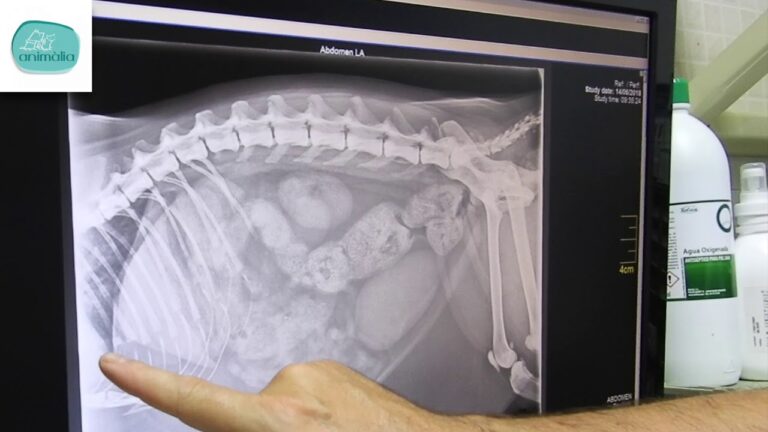

¿Qué se puede observar en una radiografía de perros?

En una radiografía de perros se pueden observar huesos, tejidos y órganos internos de la mascota, lo que es de gran utilidad para diagnosticar afecciones como cálculos en la vejiga, huesos fracturados y objetos extraños tragados. Los veterinarios pueden usar esta herramienta para tener una visión clara de lo que está ocurriendo dentro del cuerpo del animal y así determinar el mejor tratamiento posible.

El uso de radiografías en perros es fundamental para diagnosticar diferentes afecciones que afectan a sus órganos internos, tejidos y huesos. Esta herramienta permite una visión detallada del cuerpo de la mascota, lo que facilita su tratamiento y recuperación. Los veterinarios pueden detectar cálculos en la vejiga, fracturas óseas y objetos extraños tragados, entre otras patologías. La radiografía es una técnica de diagnóstico no invasiva que ayuda a los expertos en salud animal a proporcionar una atención más eficiente y efectiva.